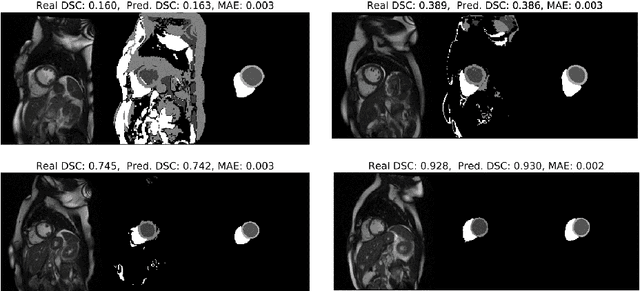

Abstract:Background: The trend towards large-scale studies including population imaging poses new challenges in terms of quality control (QC). This is a particular issue when automatic processing tools, e.g. image segmentation methods, are employed to derive quantitative measures or biomarkers for later analyses. Manual inspection and visual QC of each segmentation isn't feasible at large scale. However, it's important to be able to automatically detect when a segmentation method fails so as to avoid inclusion of wrong measurements into subsequent analyses which could lead to incorrect conclusions. Methods: To overcome this challenge, we explore an approach for predicting segmentation quality based on Reverse Classification Accuracy, which enables us to discriminate between successful and failed segmentations on a per-cases basis. We validate this approach on a new, large-scale manually-annotated set of 4,800 cardiac magnetic resonance scans. We then apply our method to a large cohort of 7,250 cardiac MRI on which we have performed manual QC. Results: We report results used for predicting segmentation quality metrics including Dice Similarity Coefficient (DSC) and surface-distance measures. As initial validation, we present data for 400 scans demonstrating 99% accuracy for classifying low and high quality segmentations using predicted DSC scores. As further validation we show high correlation between real and predicted scores and 95% classification accuracy on 4,800 scans for which manual segmentations were available. We mimic real-world application of the method on 7,250 cardiac MRI where we show good agreement between predicted quality metrics and manual visual QC scores. Conclusions: We show that RCA has the potential for accurate and fully automatic segmentation QC on a per-case basis in the context of large-scale population imaging as in the UK Biobank Imaging Study.

Abstract:Recent advances in deep learning based image segmentation methods have enabled real-time performance with human-level accuracy. However, occasionally even the best method fails due to low image quality, artifacts or unexpected behaviour of black box algorithms. Being able to predict segmentation quality in the absence of ground truth is of paramount importance in clinical practice, but also in large-scale studies to avoid the inclusion of invalid data in subsequent analysis. In this work, we propose two approaches of real-time automated quality control for cardiovascular MR segmentations using deep learning. First, we train a neural network on 12,880 samples to predict Dice Similarity Coefficients (DSC) on a per-case basis. We report a mean average error (MAE) of 0.03 on 1,610 test samples and 97% binary classification accuracy for separating low and high quality segmentations. Secondly, in the scenario where no manually annotated data is available, we train a network to predict DSC scores from estimated quality obtained via a reverse testing strategy. We report an MAE=0.14 and 91% binary classification accuracy for this case. Predictions are obtained in real-time which, when combined with real-time segmentation methods, enables instant feedback on whether an acquired scan is analysable while the patient is still in the scanner. This further enables new applications of optimising image acquisition towards best possible analysis results.